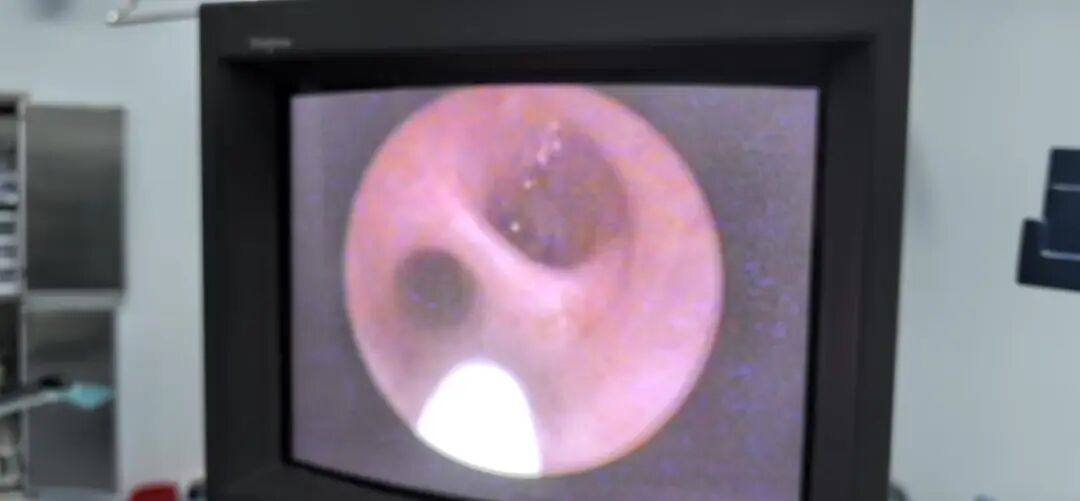

術(shù)中輸尿管鏡下可見兩條并行的輸尿管在下方匯合